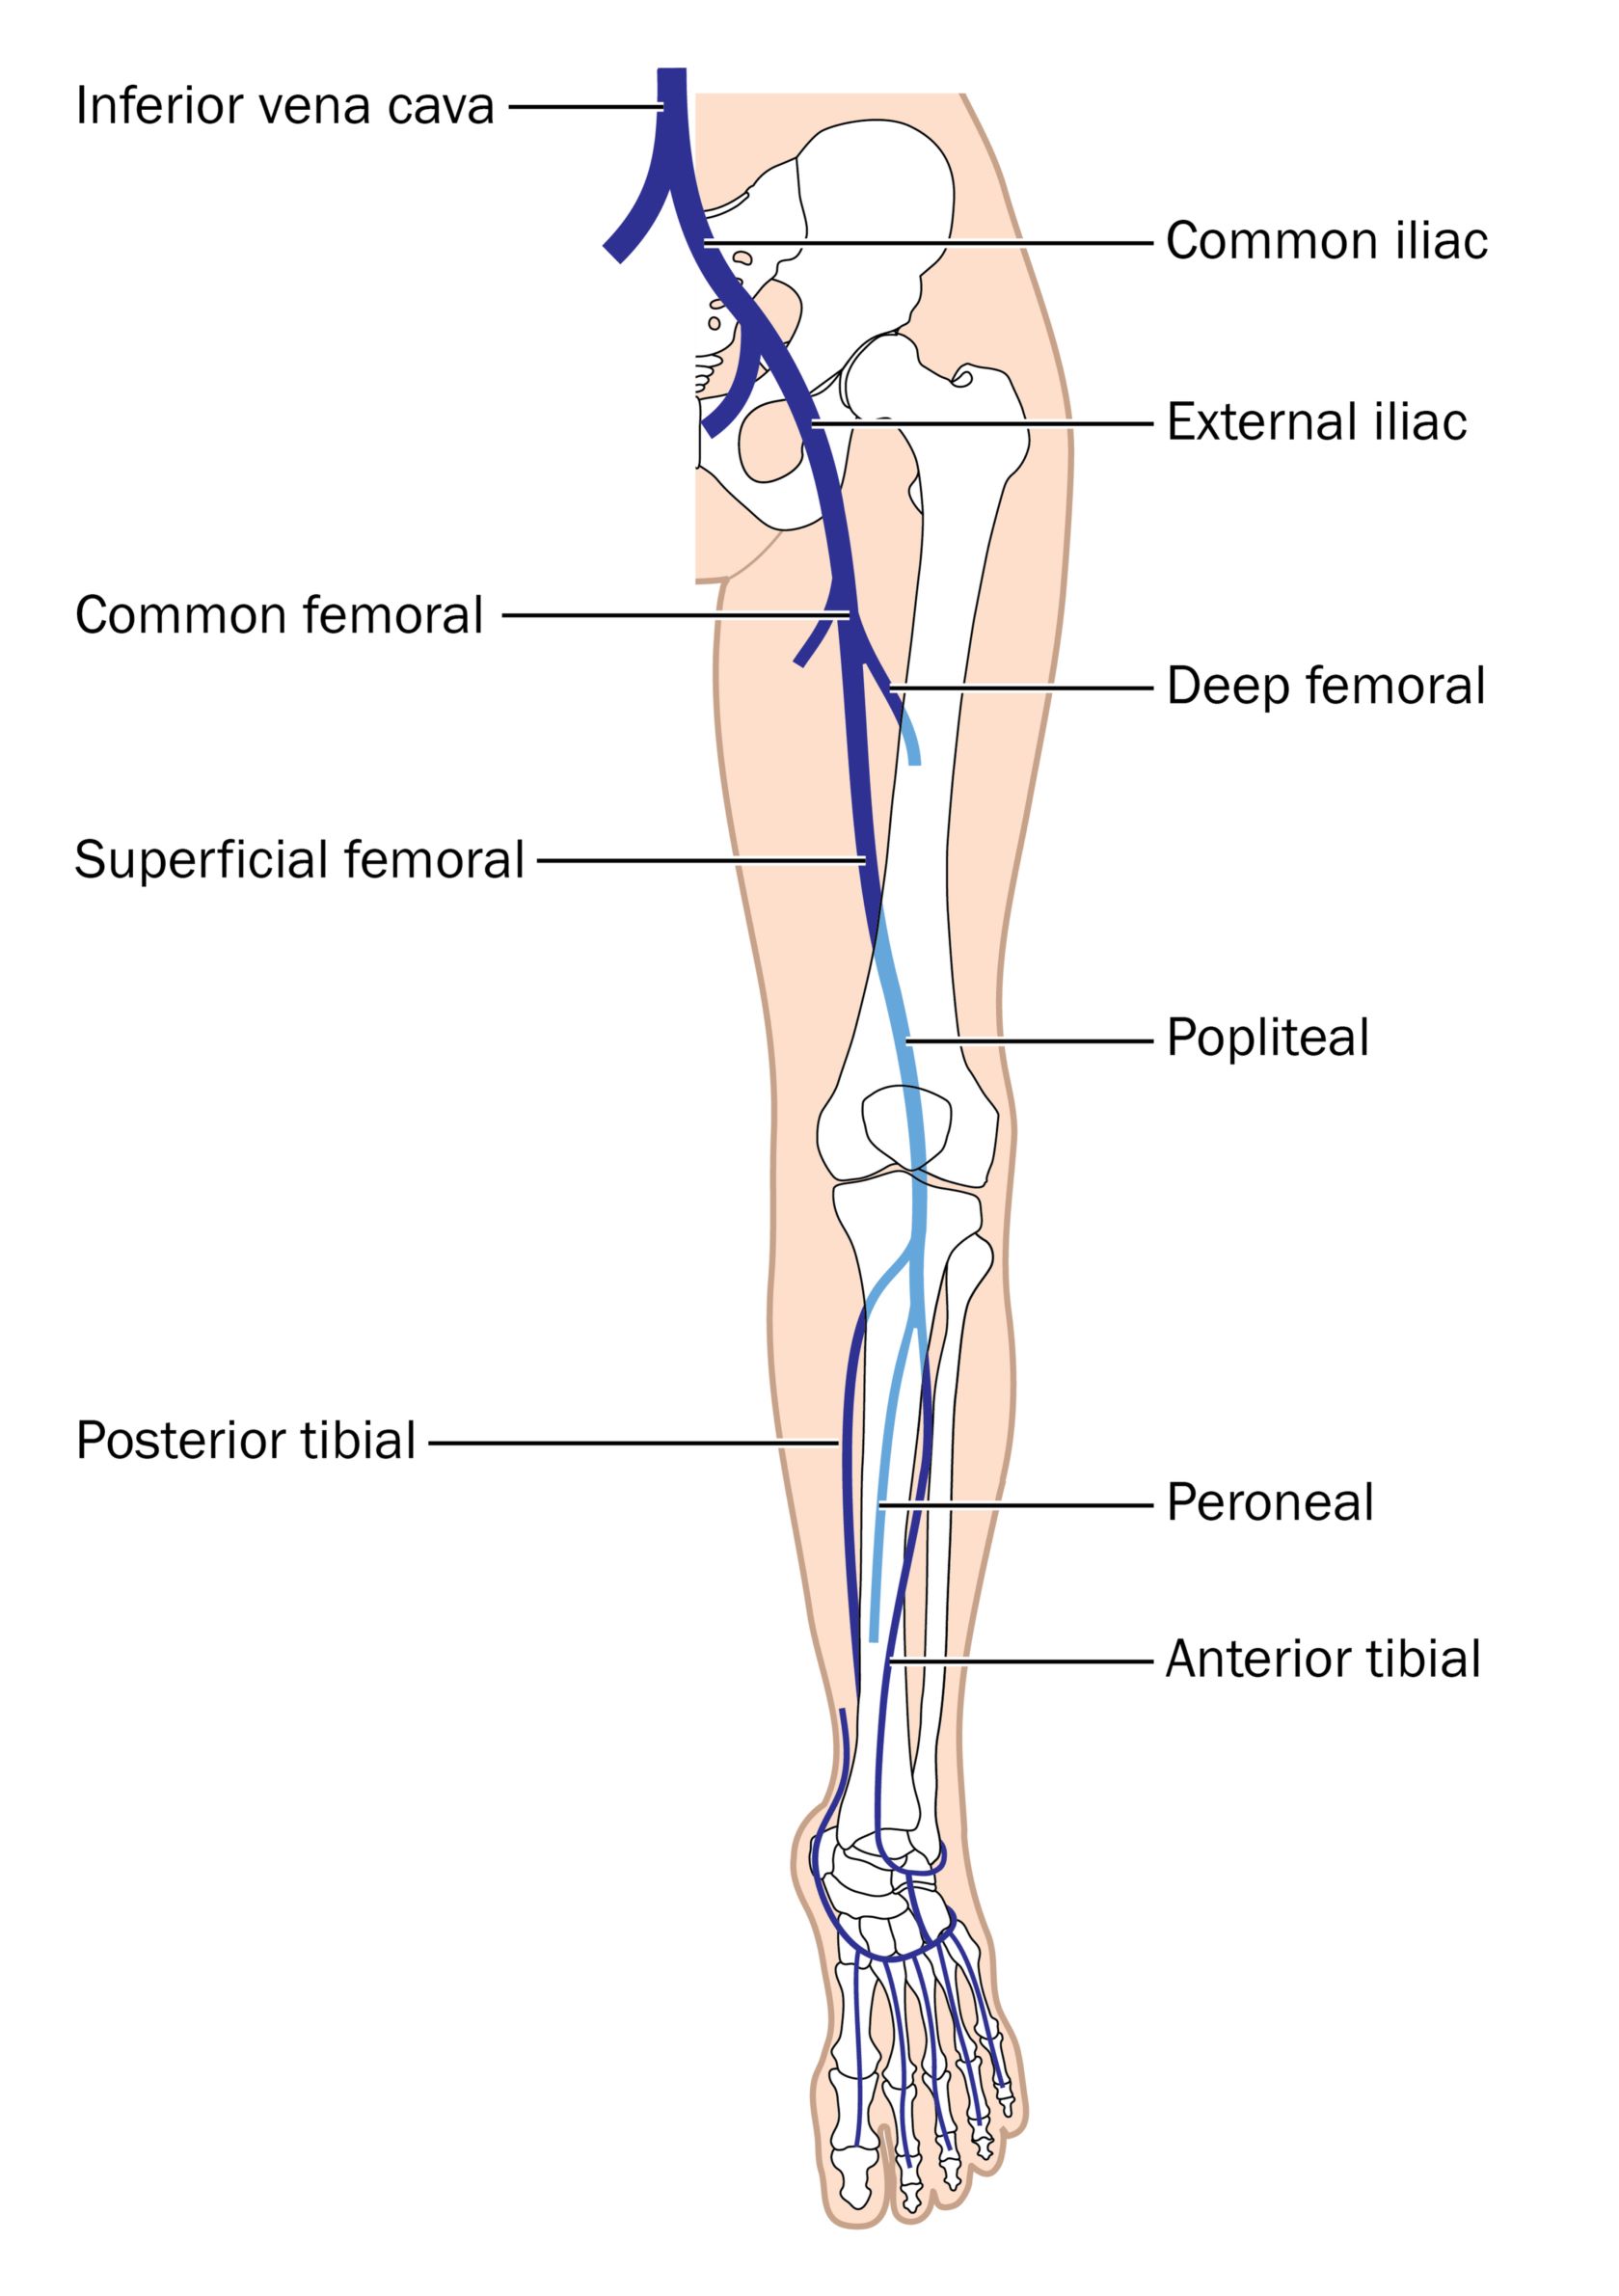

HEALTH FROM TRUSTED SOURCES: Venous Thrombosis

health-fts.blogspot.com

health-fts.blogspot.com

venous anatomy thrombosis superficial veins deep health sources trusted

Lower Extremity Deep Venous Thrombosis | Radiology Key

radiologykey.com

radiologykey.com

extremity venous thrombosis